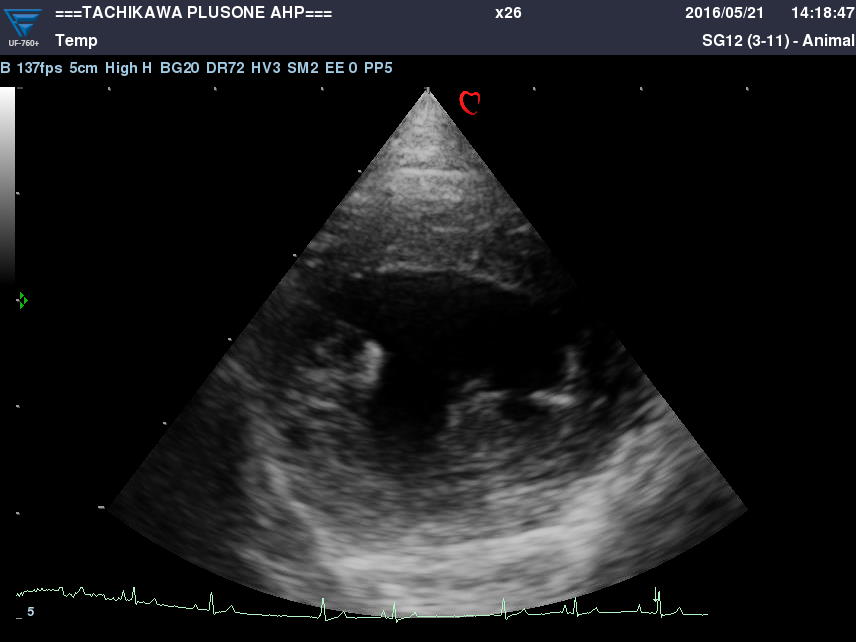

・心エコー検査(心超音波検査)

心臓の状態を把握し治療方針を決定するのに欠かせない検査です。

心臓の細部構造や動きの観察をします。

また、血液の流れる向きやスピードの計測が出来ます。